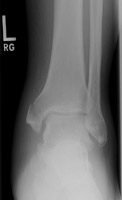

B | AP radiograph of the ankle. A bimalleolar fracture is present. |